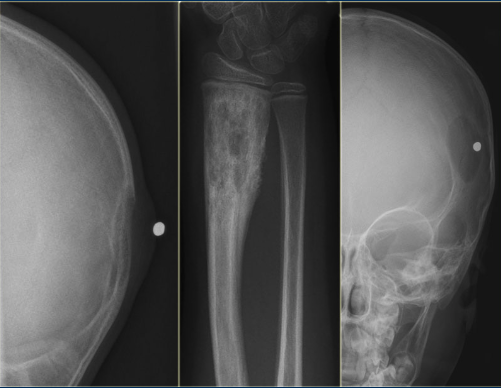

Q

Eosinophilic Granuloma

There are 3 classic appearances - for the purpose of multiple choice:

(1) Vertebra plana in a kid

(2) Skull with lucent “beveled edge” lesions (also in a kid).

(3) “Floating Tooth” with lytic lesion in alveolar ridge — this would be a differential case